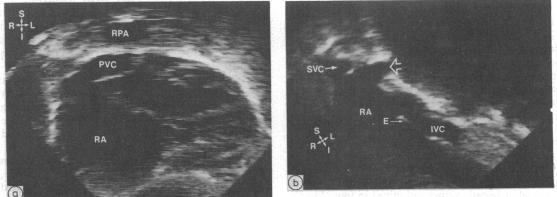

Total anomalous pulmonary venous connection can be diagnosed by cross sectional echocardiography. Information is, however, lacking concerning the diagnostic accuracy of this imaging method and any factors which may influence it. To predict the pulmonary venous connection 463 patients with congenital heart disease who had angiographic confirmation were prospectively examined. Total anomalous pulmonary venous connection was present in 34 (7%) patients and correctly detected in 33 (97% sensitivity). There were two false positive results (99% specificity). All 23 patients with atrial situs solitus with or without associated congenital heart defects were correctly detected. One false negative result occurred in a patient with right atrial isomerism and complex congenital heart disease with decreased pulmonary blood flow. Diagnosis of the type of total anomalous pulmonary venous connection, including the site and other anatomical details, was analysed and was correct in 24 of 34 (71%) patients. Errors included incorrect prediction of the site of total anomalous pulmonary venous connection in five patients with right atrial isomerism, atrioventricular canal defect, and pulmonary atresia, details of confluence interconnection in three of four patients with the mixed type of connection, undiagnosed pulmonary venous obstruction in three of the patients with right atrial isomerism, and failure to predict common pulmonary vein atresia in one patient. Factors which were related to incorrect echocardiographic diagnosis were abnormal atrial situs, mixed total anomalous pulmonary venous connection, and associated congenital cardiac defects, whereas age, weight, sex, clinical condition, and time during the study were not related. It is concluded that cross sectional echocardiography can be used to diagnose accurately total anomalous pulmonary venous connection. This method can be the definitive imaging and diagnostic method in symptomatic infants with total anomalous pulmonary venous connection who have atrial situs solitus, unifocal pulmonary venous connection, and no evidence of other major congenital cardiac defect.

完全性肺静脉异位连接可通过横断面超声心动图诊断。然而,关于这种成像方法的诊断准确性以及可能影响其的任何因素,目前尚缺乏相关信息。为预测肺静脉连接情况,对463例经血管造影证实的先天性心脏病患者进行了前瞻性检查。34例(7%)患者存在完全性肺静脉异位连接,其中33例(敏感性97%)被正确检测出。有2例假阳性结果(特异性99%)。所有23例心房正位且伴有或不伴有相关先天性心脏缺陷的患者均被正确检测出。1例假阴性结果出现在1例右心房异构且患有复杂先天性心脏病并伴有肺血流量减少的患者中。对完全性肺静脉异位连接的类型,包括部位及其他解剖细节进行了分析,34例患者中有24例(71%)诊断正确。错误包括:5例右心房异构、房室管缺损和肺动脉闭锁患者中完全性肺静脉异位连接部位预测错误;4例混合型连接患者中有3例汇合连接细节未被诊断出;3例右心房异构患者中有3例未诊断出肺静脉梗阻;1例患者未预测出共同肺静脉闭锁。与超声心动图诊断错误相关的因素为心房位置异常、混合型完全性肺静脉异位连接及相关先天性心脏缺陷,而年龄、体重、性别、临床状况及研究期间的时间与之无关。结论是,横断面超声心动图可用于准确诊断完全性肺静脉异位连接。对于有症状的完全性肺静脉异位连接婴儿,若其心房正位、肺静脉连接单一且无其他主要先天性心脏缺陷证据,该方法可作为确定性的成像和诊断方法。